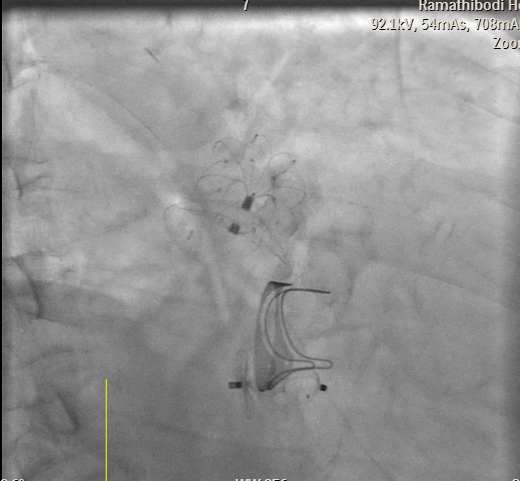

Transesophageal Echocardiography (TEE) EvaluationTEE was performed and demonstrated severe paravalvular leakage of the bioprosthetic mitral valve at the 3 o¡¯clock position.Vascular Access PreparationBoth groins were infiltrated with 10 mL of 2% lidocaine for local anesthesia. Using the front-wall technique, a 6F sheath was inserted into the right femoral vein and subsequently upsized to a 12F FastCath introducer sheath. The left femoral artery was cannulated with a 6F sheath for continuous arterial pressure monitoring.Transseptal PunctureA 0.032-inch guidewire was advanced into the superior vena cava, followed by placement of an 8.5F SL1 introducer. A BRK 18-gauge transseptal needle was introduced with the needle tip kept within the sheath.Under TEE and fluoroscopic guidance, the system was slowly withdrawn into the right atrium to identify the optimal puncture site. A successful mid-posterior transseptal puncture was achieved into the left atrium.Hemodynamics recorded LA pressure of 12 mmHg with a peak V-wave of 19 mmHg.Crossing the Paravalvular Leak (PVL)A 0.032-inch wire was advanced across the PVL, and the 8.5F Agilis catheter was positioned in the left atrium.Wire and Catheter Exchange for PVL CrossingA 6F MP01 guiding catheter was directed toward the medial aspect of the mitral valve. A 0.035-inch Terumo wire crossed into the left ventricle and was exchanged for an Amplatz Super Stiff wire.Sheath ExchangeThe 6F MP guiding catheter and 8.5F Agilis sheath were removed and replaced with a 7F DuraSheath (90 cm) to provide adequate support.First Attempt at PVL ClosureAn Amplatzer Vascular Plug III (AVP III) 5 ¡¿ 10 mm was delivered across the defect. Despite optimal positioning, the device did not achieve complete occlusion of the PVL.Successful PVL ClosureThe Trevisio 8F delivery system replaced the 7F DuraSheath. A larger AVP III 5 ¡¿ 14 mm device was advanced across the defect and deployed.After position adjustment, the device was released. TEE confirmed a stable device position with no residual PVL. All equipment was removed, and the venous access was upsized to a 14F FastCath introducer to prepare for LAA occlusion.Transition to LAA Occlusion PhaseA 10F Lambre delivery sheath was advanced into the left upper pulmonary vein (LUPV), replacing the SL1 sheath.Accessing the LAAA 5F pigtail catheter was inserted, and the delivery sheath was advanced into the LAA under fluoroscopic and TEE guidance.Device PreparationA 38/34 mm Lambre LAA occlusion device was prepared and loaded into the delivery system.LAA Occlusion DeploymentThe device was deployed just proximal to the LAA ostium. Stability and seating were confirmed using angiography and TEE.LAA angiography demonstrated trace residual flow into the LAA. The device was then detached.Real-time 3D TEE confirmed proper positioning with no significant peridevice leak.Hemostasis and CompletionAll delivery systems were removed. Venous hemostasis was achieved using a figure-of-eight suture, and arterial access was sealed with manual compression. The procedure was completed without immediate complications.